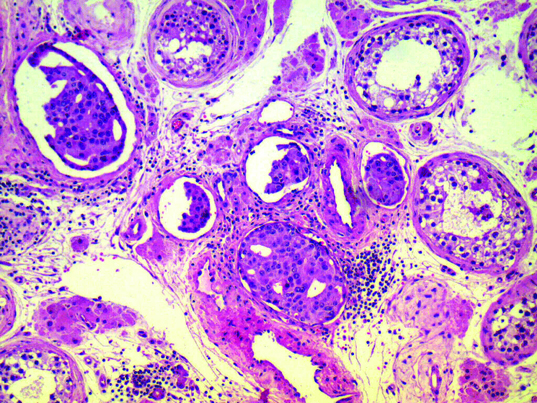

Malignant glands and single cells seen infiltrating in between the seminiferous tubules (200X magnification); H&E

A 63-year-old male presented in the Urology department with symptoms of difficulty in micturition for which he was investigated with Ultrasound Kidney-urinary bladder (USG KUB) and found to have enlarged prostate. Serum prostate specific antigen (PSA) was 225.49 ng/ml at presentation and Tru-cut biopsy from both lobes of prostate reported acinar adenocarcinoma prostate, with tumour involving 65% of submitted tissue with peripheral invasion and Gleason’s score (GS = 4+4) = 8. Magnetic Resonance Imaging (MRI) of Pelvis showed enlarged prostate measuring 49x39 mm with nodular enlargement of central zone and T2W hyper intense signal in peripheral zone without any peri-prostatic extension and a small lymph node 7mm in right external iliac region. He underwent Radionuclide Technetium (99m TC- MDP) bone scan which showed skeletal metastasis involving twelfth dorsal (D12) vertebrae and right ischium [Table/Fig-1]. The patient was advised for androgen deprivation therapy (ADT) and he opted for surgical castration. He underwent bilateral orchiectomy and histopathology reported to be metastatic adenocarcinoma of right testis [Table/Fig-2] and the resection margin of right spermatic cord showed lymphovascular invasion [Table/Fig-3]. The other testis was absolutely normal. His serum PSA started falling, 134.84 ng/ml after 1 month of orchiectomy and he was started on hormonal therapy and palliative radiation to the bony metastatic sites.